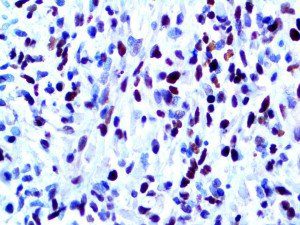

It is the ICU physician who is most likely to witness one of the deadliest manifestations of the abnormal immunological response, the cytokine storm syndrome (CSS). This response is also referred to by some as the cytokine release syndrome (CRS). CSS is characterized by continuous activation and expansion of macrophage and lymphocyte populations, which secrete large amounts of cytokines, causing the cytokine storm. This massive cytokine release is akin to hemophagocytic lymphohistiocytosis (HLH) disease, a syndrome characterized by initial unchecked and persistent activation of cytotoxic T lymphocytes and NK cells.

Clinical and laboratory manifestations of HLH include fever, enlarged liver and/or spleen, neurologic dysfunction, coagulopathy, liver dysfunction, cytopenias (i.e., low levels of erythrocytes, leukocytes, and/or platelets), hypertriglyceridemia, hyperferritinemia, hemophagocytosis, and eventually diminished NK cell activity as the immune system becomes progressively paralyzed. HLH can be familial (primary HLH) or secondary to another disease process (sHLH), such as rheumatic disease, in which it is referred to as macrophage activation syndrome (MAS, characterized by elevated ferritin).